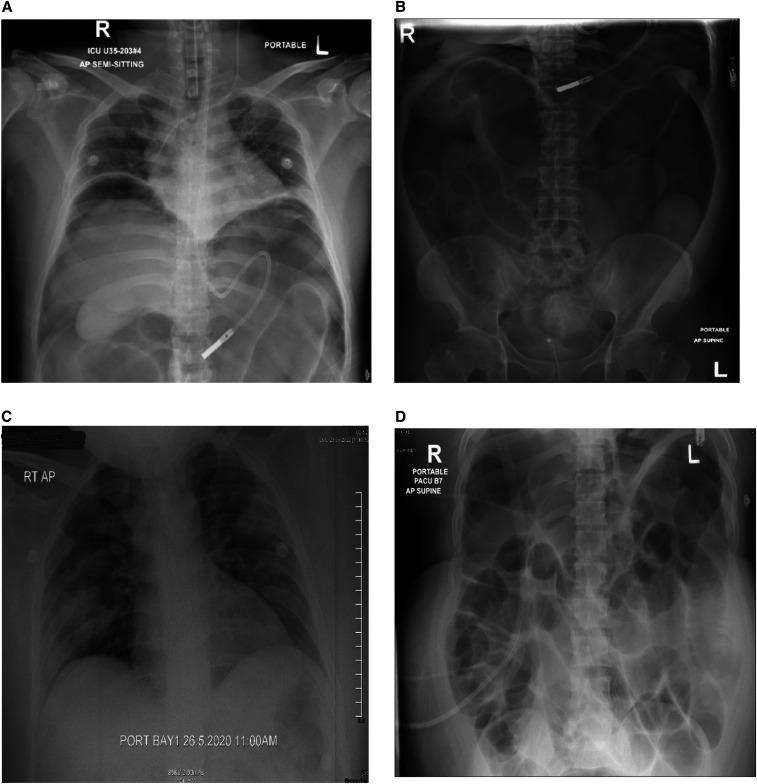

The COVID-19 pandemic has recently spread worldwide, presenting primarily in the form of pneumonia or other respiratory disease. In addition, gastrointestinal manifestations have increasingly been reported as one of the extrapulmonary features of the virus. We report two cases of SARS-CoV-2 infection complicated by paralytic ileus. The first patient was a 33-year-old man who was hospitalized with severe COVID-19 pneumonia requiring ventilator support and intensive care. He developed large bowel dilatation and perforation of the mid-transverse colon, and underwent laparotomy and colonic resection. Histopathology of the resected bowel specimen showed acute inflammation, necrosis, and hemorrhage, supporting a role for COVID-19-induced micro-thrombosis leading to perforation. The second patient was a 33-year-old man who had severe COVID-19 pneumonia, renal failure, and acute pancreatitis. His hospital course was complicated with paralytic ileus, and he improved with conservative management. Both cases were observed to have elevated liver transaminases, which is consistent with other studies. Several authors have postulated that the angiotensin-converting enzyme 2 receptors, the host receptors for COVID-19, that are present on enterocytes in both the small and large bowel might mediate viral entry and resultant inflammation. This is a potential mechanism of paralytic ileus in cases of severe COVID-19 infection. Recognizing paralytic ileus as a possible complication necessitates timely diagnosis and management.

新型冠状病毒肺炎(COVID-19)疫情近期在全球蔓延,主要表现为肺炎或其他呼吸道疾病。此外,越来越多的研究报告称,胃肠道表现是该病毒的肺外特征之一。我们报告了两例由 SARS-CoV-2 感染引起的麻痹性肠梗阻病例。第一例患者是一名 33 岁男性,因重症 COVID-19 肺炎需要呼吸机支持和重症监护而住院。他出现大肠扩张和横结肠中段穿孔,并接受了剖腹手术和结肠切除术。切除肠标本的组织病理学检查显示急性炎症、坏死和出血,支持 COVID-19 引起的微血栓形成导致穿孔的作用。第二例患者是一名 33 岁男性,患有重症 COVID-19 肺炎、肾衰竭和急性胰腺炎。他的住院过程中并发麻痹性肠梗阻,经保守治疗后好转。这两例患者的肝转氨酶均升高,这与其他研究结果一致。一些作者推测,COVID-19 的宿主受体血管紧张素转换酶 2(angiotensin-converting enzyme 2,ACE2)受体存在于小肠和大肠的肠上皮细胞中,可能介导病毒进入和由此产生的炎症。这是严重 COVID-19 感染导致麻痹性肠梗阻的潜在机制。认识到麻痹性肠梗阻可能是一种并发症,需要及时诊断和治疗。